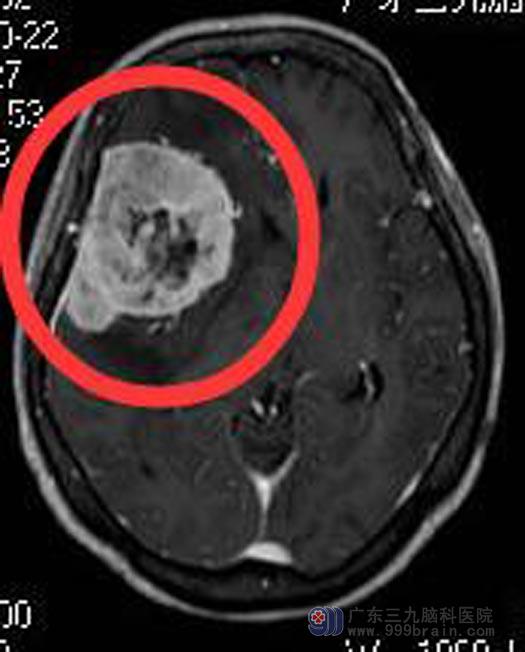

儿女们带着她来到广东三九脑科医院综合神经外科。头颅MR检查提示:右侧颞部占位性病变,范围约为6.0cm×4.5cm×6.0cm。头颅CTA检查提示:右侧颞部巨大占位,血供丰富,其内可见血管分布,周缘较多血管缠绕,邻近右侧大脑中动脉明显受压移位,邻近血管部分可疑被包绕。鲁明主任建议先行肿瘤部分供血血管栓塞,再行手术切除。

手术前